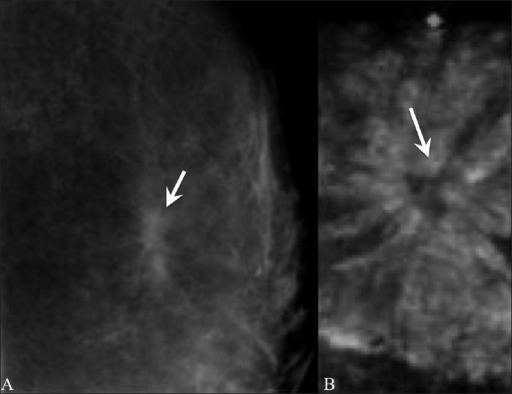

Intraductal papilloma

This condition, also called papillary neoplasm, is a wart-like growth that develops inside a breast duct near the nipple. Usually detected on mammogram, or patient may present with a lump or nipple discharge. It is most common in women aged 35-55. Further testing is required to exclude breast cancer. Single papillomas with no abnormalities do not increase a women’s risk of breast cancer, but those with papillomatosis (multiple papillomas) have a slightly elevated risk. Regular surveillance is advised for this cohort.

Diagnostic value of 3D fast low-angle shot dynamic MRI of breast papillomas. by E. J. Son, E. K. Kim, J. A. Kim, J. Y. Kwak, J. Jeong is licensed under CC BY-NC 3.0